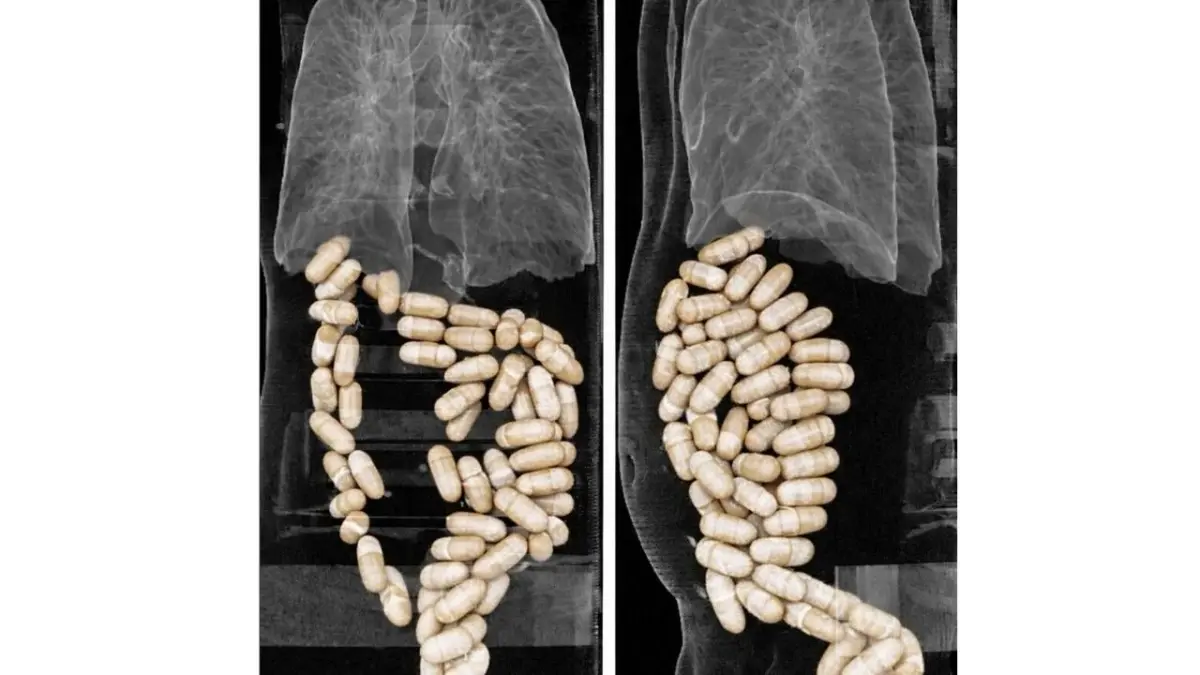

İzmir'de, havalimanında gözaltına alınan 2 şüphelinin midesinden 127 kapsül halinde toplam 1 kilo 304 gram uyuşturucu çıktı. Şüpheliler çıkarıldıkları mahkemede tutuklandı.

Narkotik Suçlarla Mücadele Şube Müdürlüğü ekipleri, istihbarat çalışmasıyla yurt dışından 2 şüphelinin kapsül halindeki uyuşturucu maddeyi yutarak Türkiye'ye getirecekleri bilgisine ulaştı. Ekipler, bunun üzerine önceki gün, İzmir Adnan Menderes Havalimanı'nda önlem aldı. Hastaneye sevk edilen E.E. ve N.M.'nin yapılan radyolojik görüntülemelerinde, midelerinde toplam 127 kapsül halinde toplam 1 kilo 304 gram eroin olduğu ortaya çıktı. Midelerindeki kapsüller İzmir Katip Çelebi Üniversitesi (İKÇÜ) Atatürk Eğitim ve Araştırma Hastanesi'nde doğal yollarla çıkartılan E.E. ve N.M., sevk edildikleri adliyede çıkarıldıkları mahkemede tutuklandı.